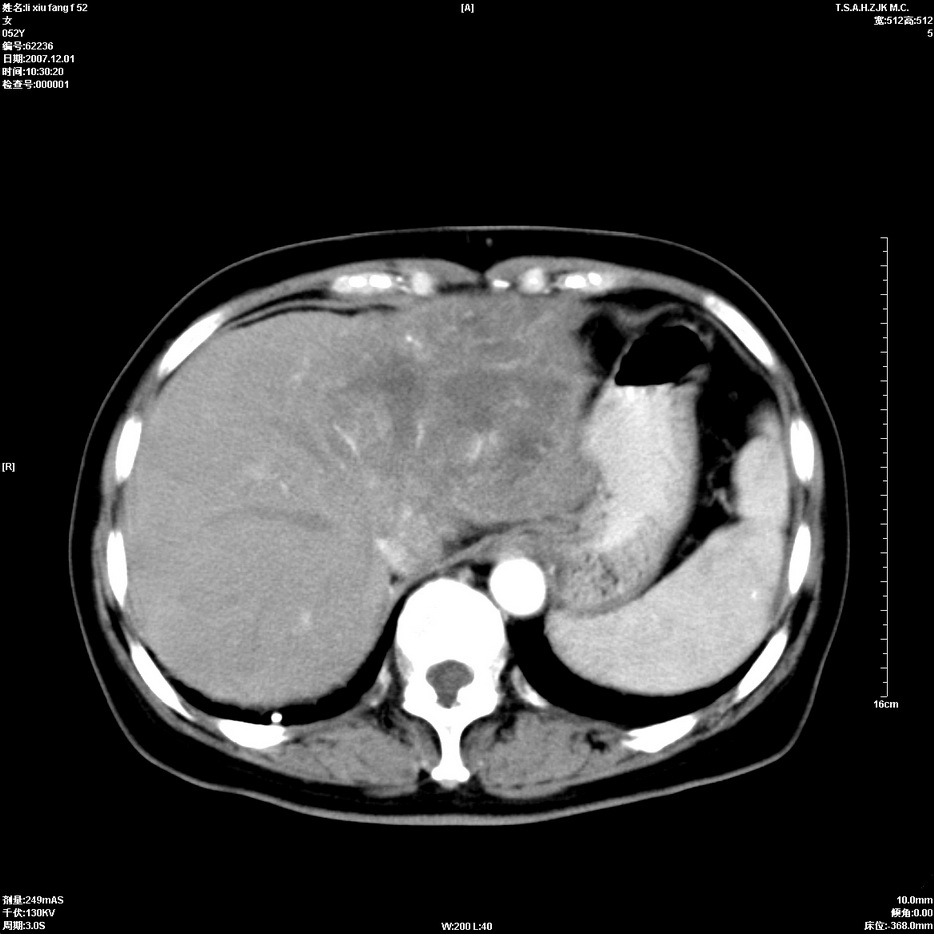

标题: CT12858:女,52岁,胎甲球蛋白861肝左叶占位,肝癌。下腔静 [打印本页]

标题: CT12858:女,52岁,胎甲球蛋白861肝左叶占位,肝癌。下腔静

肝左叶巨大低密度灶肿块,增强符合快进快出表现,有动静脉交通支;静脉期,下腔静脉内有充盈缺损,afp明显升高,支持肝癌并下腔静脉癌栓形成。

支持楼主   门静脉主干及左支癌栓形成

以下是引用拾荒者在2008-4-15 22:57:00的发言:[br]肝左叶巨大低密度灶肿块,增强符合快进快出表现,有动静脉交通支;静脉期,下腔静脉内有充盈缺损,afp明显升高,支持肝癌并下腔静脉癌栓形成。